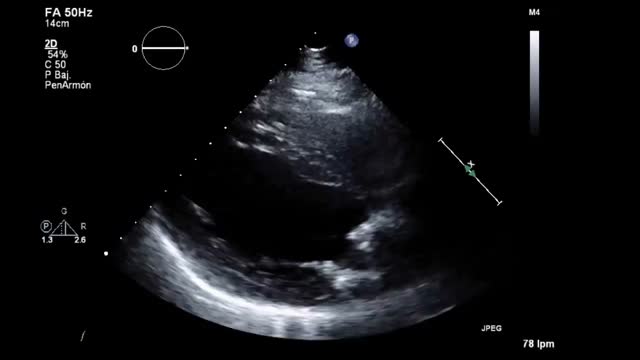

Valoración de la volemia y gradiente dinámico (Video 1 en material suplementario)La valoración de la volemia a través de los ultrasonidos resulta compleja y requiere su integración con la exploración clínica. En el PC no son aplicables algunos conceptos clásicos de respuesta a volumen por la alta incidencia de arritmias, disfunción ventricular, HTP, cor pulmonale crónico, enfermedades vasculares y reemplazo valvular. Sin embargo, la ecocardiografía aporta un valor añadido a otros dispositivos, especialmente en la valoración de área telediastólica ventricular, la variación del flujo Doppler transmitral y del TSVI, así como la colapsabilidad de la vena cava inferior (tabla 2).

Uno de los cuadros clínicos más difíciles de manejar en el PC es la insuficiencia mitral que se produce por un movimiento anómalo de la valva anterior (SAM), generando un gradiente de presión en el TSVI o mesoventricular, arrastrando y succionando la valva anterior mitral (fig. 3). Debe sospecharse en casos con hipertrofia concéntrica, miectomía o implante de prótesis mitral con postes grandes que se dirigen hacia el TSVI, estados de hipovolemia y/o necesidad de soporte vasoactivo ascendente sin respuesta tensional apropiada.

PC de bypass coronario en paciente con hipertrofia del VI concéntrica: obstrucción dinámica TSVI por exceso de soporte inotrópico e hipovolemia postoperatoria, generando insuficiencia mitral severa por movimiento septal anterior (SAM). Obsérvese el flujo de aceleración progresiva por Doppler continuo.